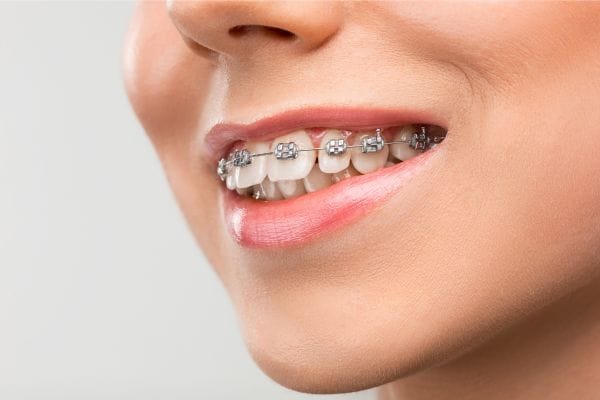

3. Instalación de brackets

Con el plan de tratamiento claro, llega el momento de la instalación de los brackets. Este procedimiento, aunque sencillo, requiere precisión. Primero, el ortodoncista limpia a fondo la superficie de los dientes para asegurar una correcta adhesión. Luego, aplica un adhesivo dental especial y coloca los brackets en cada diente. A continuación, se conecta un arco metálico a los brackets, que será el responsable de aplicar la presión necesaria para mover los dientes a la posición deseada.

Durante este proceso, se ajusta la tensión del arco metálico para asegurar que los dientes se muevan gradualmente. El procedimiento completo puede durar entre una y dos horas, dependiendo de la complejidad del caso.